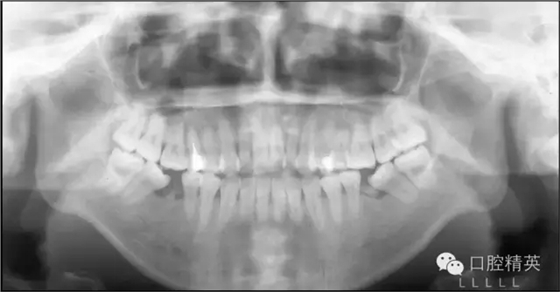

自上個世紀末開始至今,微螺釘種植體支抗在正畸領(lǐng)域的應用已有近20年的歷史。而隨著其被越來越廣泛靈活地應用于正畸臨床工作中,其在垂直向上的獨特優(yōu)勢也越來越突出,大致可以歸納為以下六個方面:高角病例全方位垂直向控制;改善露齦微笑——壓低上前牙;打開重度深覆合——壓低下前牙或同時壓低上前牙;矯正平面傾斜——壓低一側(cè)牙齒;壓低過萌長磨牙——壓低磨牙;直立近中傾斜的磨牙——直立并壓低磨牙。本文將以結(jié)合典型病例的方式對以上六種微螺釘種植體支抗在垂直向上的應用一一論述說明。

Ⅰ類或Ⅱ類高角,前牙開合,但前牙垂直向唇齒關(guān)系正常,即沒有露齦微笑。這類高角病例將最直接而有效地發(fā)揮微螺釘種植體支抗在垂直向上的優(yōu)勢。在后部,應用微螺釘進行后部垂直向控制,壓低后牙,解除支點,下頜平面前上旋轉(zhuǎn),前牙開合關(guān)閉。在前部,因為沒有露齦微笑的問題,上前牙并不需要實現(xiàn)絕對壓低,僅需保持住其垂直向位置,阻止因上前牙的伸長而導致下頜平面前上旋轉(zhuǎn)的空間減小。

因此,即使對于拔牙病例因鐘擺效應上前牙有伸長趨勢,通過直絲弓矯治技術(shù)中的搖椅弓也能夠很好地實現(xiàn)前部的垂直向控制。這類高角患者的全方位垂直向控制充分說明,后部垂直向控制,即磨牙的絕對壓低或相對壓低(向遠中直立或阻止其伸長)是實現(xiàn)下頜平面前上旋轉(zhuǎn)的必要條件,而后上移動上前牙的前部垂直向控制并不是必需的,僅需控制即可,甚至上前牙稍有伸長,因為沒有露齦微笑,只要下頜平面可以前上旋轉(zhuǎn)到一個理想的位置,頦部位置和形態(tài)得到顯著的改善,也是完全可以接受的。